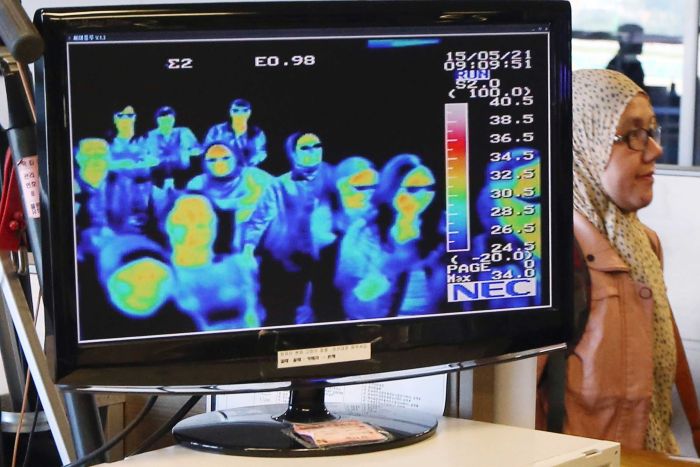

Some countries use thermal scanners to detect people with fevers, but they probably aren’t a useful intervention at this stage because people who are sick may not have a raised temperature all the time, Dr Cheng said.

“So it will miss lots of people who do have [a disease that causes] fever,” he said.

“And for people who do have fever, especially during the northern hemisphere influenza season, there’s a good chance that it’s not this novel coronavirus.”